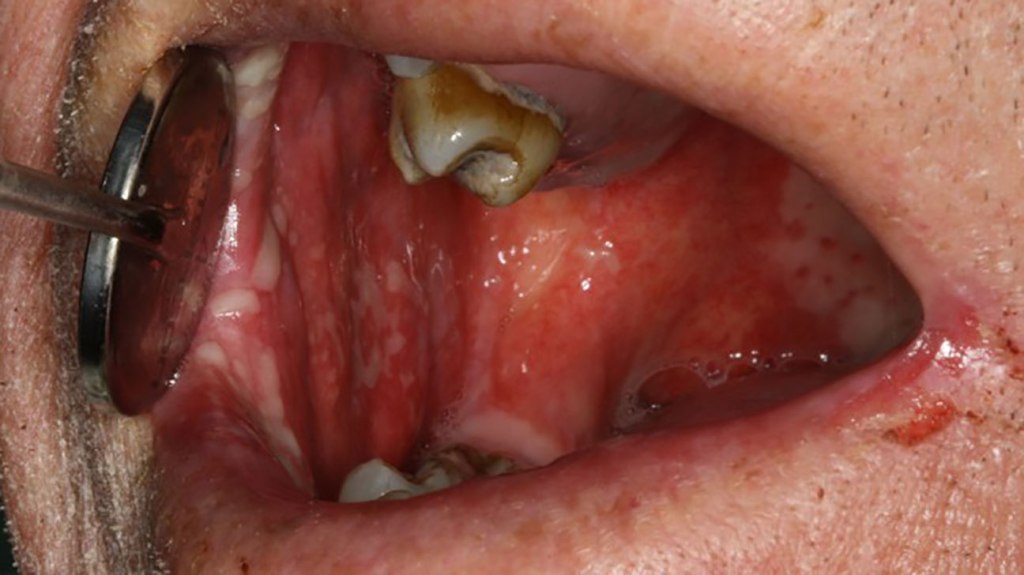

This is something that happens whenever chemotherapy drugs are used, as they attack both the bad, but also the good cells within this. Basically, this attacks the ones within the lining of the mouth, causing ulcers, infections, and the like. It also weakens the immune system, and it can reduce the resistance to fight this off. Some of the common symptoms of mucositis include:

- Sores, a red, or swollen mouth

- Lesions and ulcers

- A mouth that bleeds

- White pus or patches within the mouth

There are other tissues that get impacted by this too, including gums and the tongue, and these get impacted.This can make eating, swallowing, and even talking quite painful. It also causes intolerance to drinks and foods, and this causes dehydration, or malnutrition too in some people. This can also cause what’s called lichenoid mucositis too in some cases.